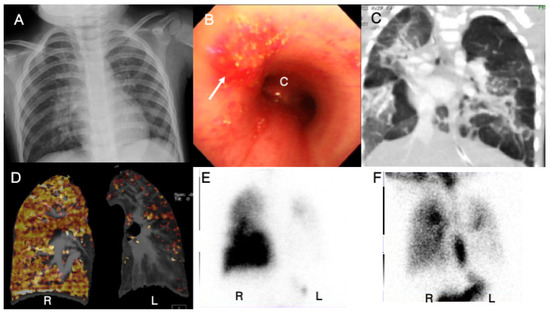

3.7. Case 7